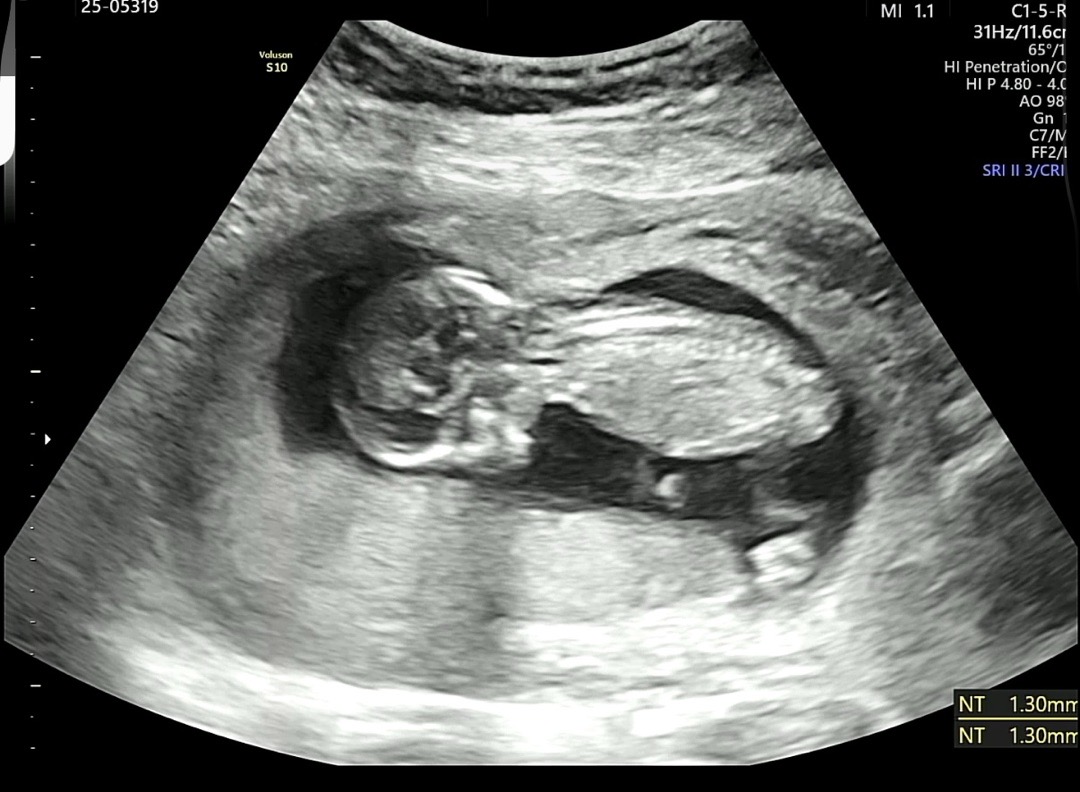

아기 성별 봐주실 분 ⵑ ㅠ 13주 입니당

둘째인데 13주에 초음파 보고 와써요 각도법으로 볼 수 있는 각도가 안나온거 같긴한데 너무 궁금해서 고수님들 계실까 싶어 올려봅니당.. 넘 궁금해서용 ㅎㅎ 사진 댓글에 여러장 올릴께욘.. ˃̵͈̑ᴗ˂̵͈̑

사진추가해용